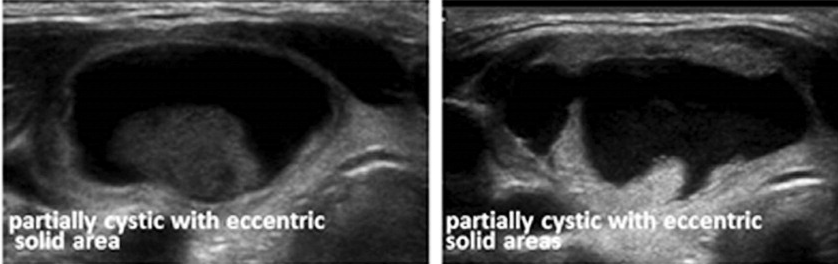

유투브와 블로그를 통해서 초음파영상 보는 방법을 충분히 숙지한 상태였기 때문에 검사와 동시에 모니터로 송출되는 영상을 보면서 그때그때 궁금한 점들을 검사자에게 물어보았다.

초음파검사는 갑상선암 결절을 중심을 시작으로 주변으로 범위를 넓혀가는 방식으로 검사를 진행하였고, 검사 중간에 진찰을 했었던 의사가 들어와 직접 초음파영상을 보면서 상태에 대한 설명을 해주었다.

"음, 다행히도 갑상선암 부위는 초음파영상에서는 별다른 변화나 의심되는 점이 발견되지 않네요. 그래도, 암은 분명하니 대학병원 정밀 진찰 및 검사를 한 번 더 받아보시길 권합니다."하고 무미건조하게 말하고 검사실을 나갔다.